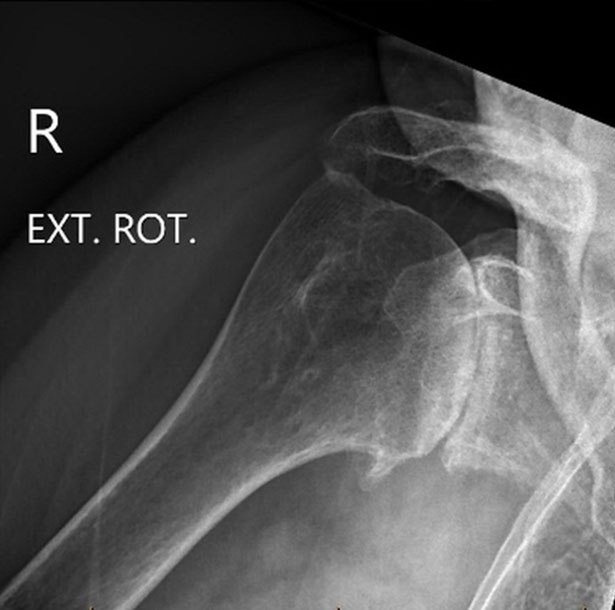

Shoulder before replacement surgery

Move the slider to compare arthritic shoulder with stemless replacement